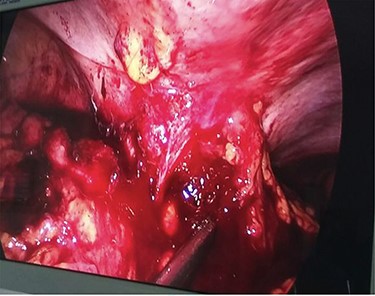

Ascending colonic cancer complicated by an anterior abdominal wall abscess was diagnosed. Exploratory laparotomy was performed and a right colonic mass ~9 × 8 cm in diameter was found, which was widely adherent to the lateral abdominal wall, with extension through a fistulous track into the subcutaneous tissue (Fig. 4). There was no distant metastasis. Extended right hemicolectomy and lymph node dissection was performed with limited resection (en bloc) of the involved part of the lateral abdominal wall using a closure technique.

Diagnostic laparoscopy showing ascending colon adherent to anterior abdominal wall.